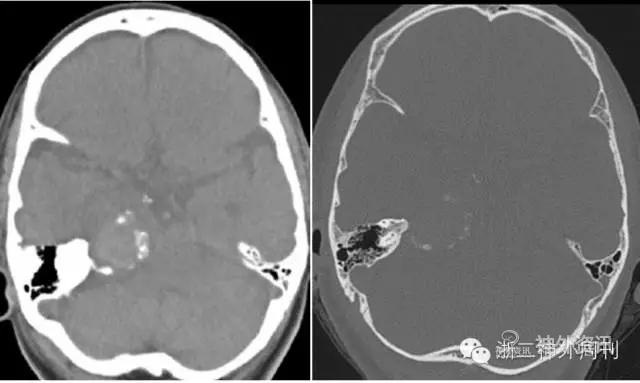

头颅CT及骨窗示:右岩骨尖旁见一肿块,周围伴蛋壳状钙化,周围骨质未见明显破坏(图3)。

图3. CT平扫及骨窗位显示右岩骨尖旁见一肿块,周围伴蛋壳状钙化。